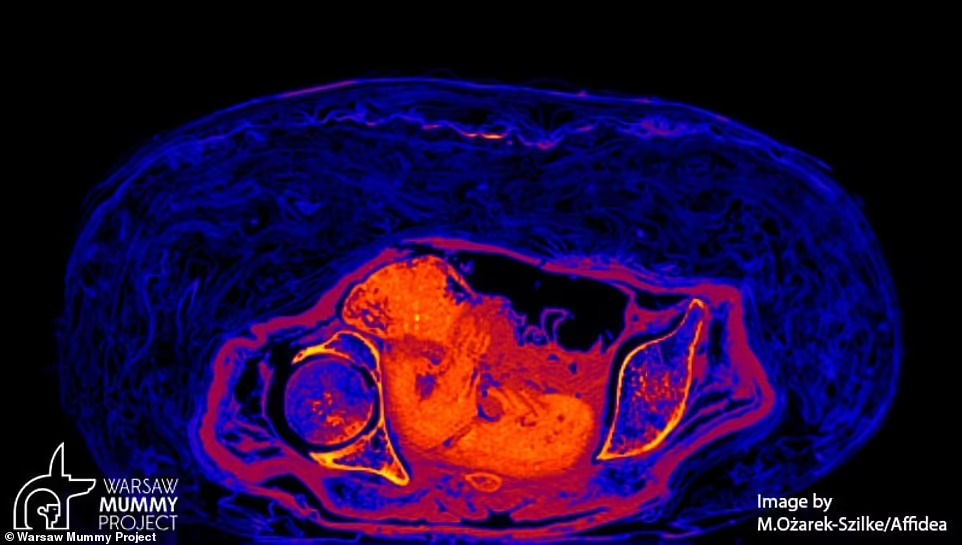

كشفت دراسة جديدة، أن أول مومياء مصرية حامل، كانت مصابة بالسرطان، ومن المحتمل أن تكون جثتها عمرها 2000 عام.

ومن المعروف بالفعل أن المرأة، الملقبة بـ السيدة الغامضة، توفيت أثناء حملها لمدة 28 أسبوعًا، لكن الباحثين الآن حددوا سبب الوفاة.

وأضاف ستيك، أن صغر سن المومياء وعدم وجود سبب آخر للوفاة، يشير إلى أن إصابتها بالسرطان كانت السبب في وفاتها.